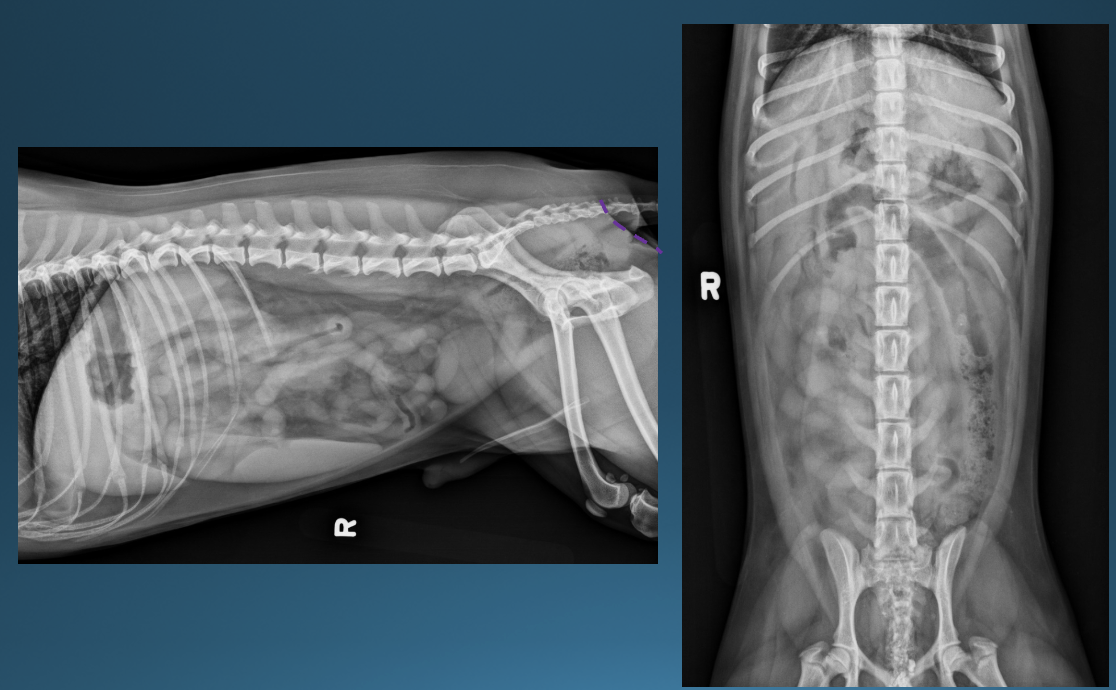

What is shown in these images?

peritonitis